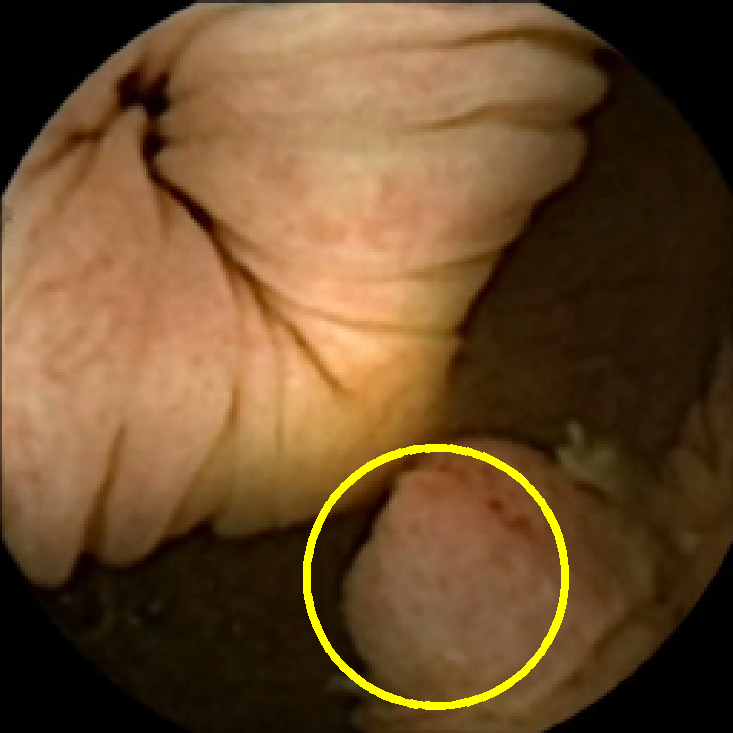

In Figure 5 we show the circles of radius corresponding to the features that were correctly classified as polyps by (29). We observe that the classifier was able to identify the polyps of a variety of shapes even in the presence of small amounts of trash liquid (first row) or when the polyps are located next to mucosal folds (rows two to four in column (c)).